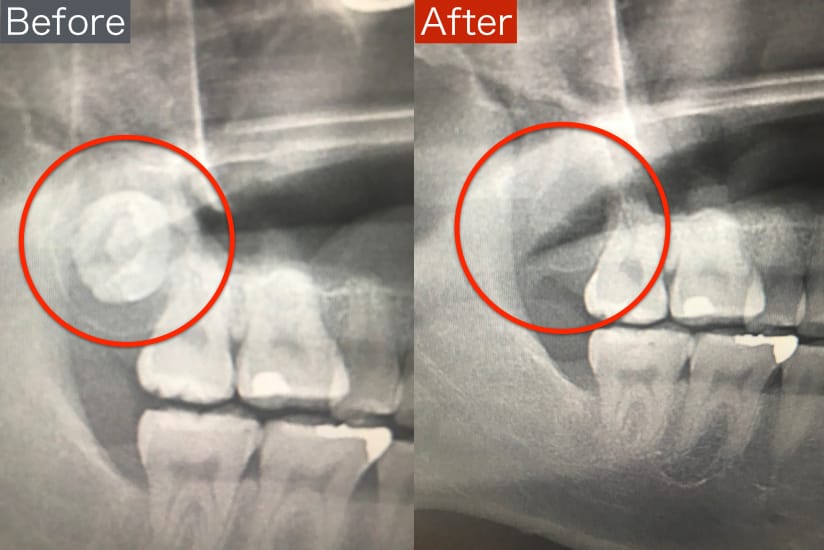

前医でインプラントの埋入角度が悪く、インプラント周囲炎になってしまった患者様の症例です。

インプラントが虫歯になることはありませんが、インプラント周囲炎というインプラントの歯周病にはなります。

インプラント周囲炎の主な原因は汚れ(菌)と力です。このように斜めに埋入されているインプラントは、真っ直ぐ埋入されているものに比べて汚れも溜まりやすく、噛む力も斜めにかかってしまうため、インプラント周囲炎になるリスクが大幅に高くなります。

この患者様は内側の骨が大幅に溶けてしまっていたので、前のインプラントを撤去して、骨を再生させると同時にインプラントを正しい位置と角度で埋入し直しました。溶けてしまっていた骨が治っていることもレントゲンでご確認いただけるかと思います。

インプラントは「どこの位置にどのような角度で入れるか」によって、一生使い続けられるかどうかの期待値が大きく異なります。値段だけを基準にクリニックを決めるのではなく、信用できる歯医医師と治療を進めることをお勧めします。